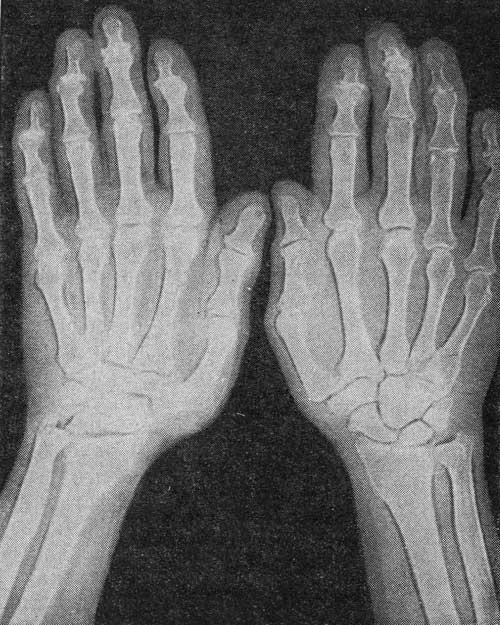

Симптомы и лечение остеоартроза узелков Гебердена: фотогалерея